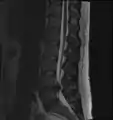

L'imagerie par résonance magnétique peut montrer la hernie, le canal vertébral, les nerfs, les tissus environnants. Les tissus mous sont les mieux analysés par cet examen qui est le plus performant pour le diagnostic de hernie discale. Les images pondérées en T2 montrent clairement la hernie.

IRM lombosacrée sagittale montrant une hernie discale de niveau L4-L5. IRM lombosacrée sagittale montrant une hernie discale de niveau L4-L5.

IRM lombaire sagittale montrant une hernie discale de niveau L4-L5. IRM lombaire sagittale montrant une hernie discale de niveau L4-L5.